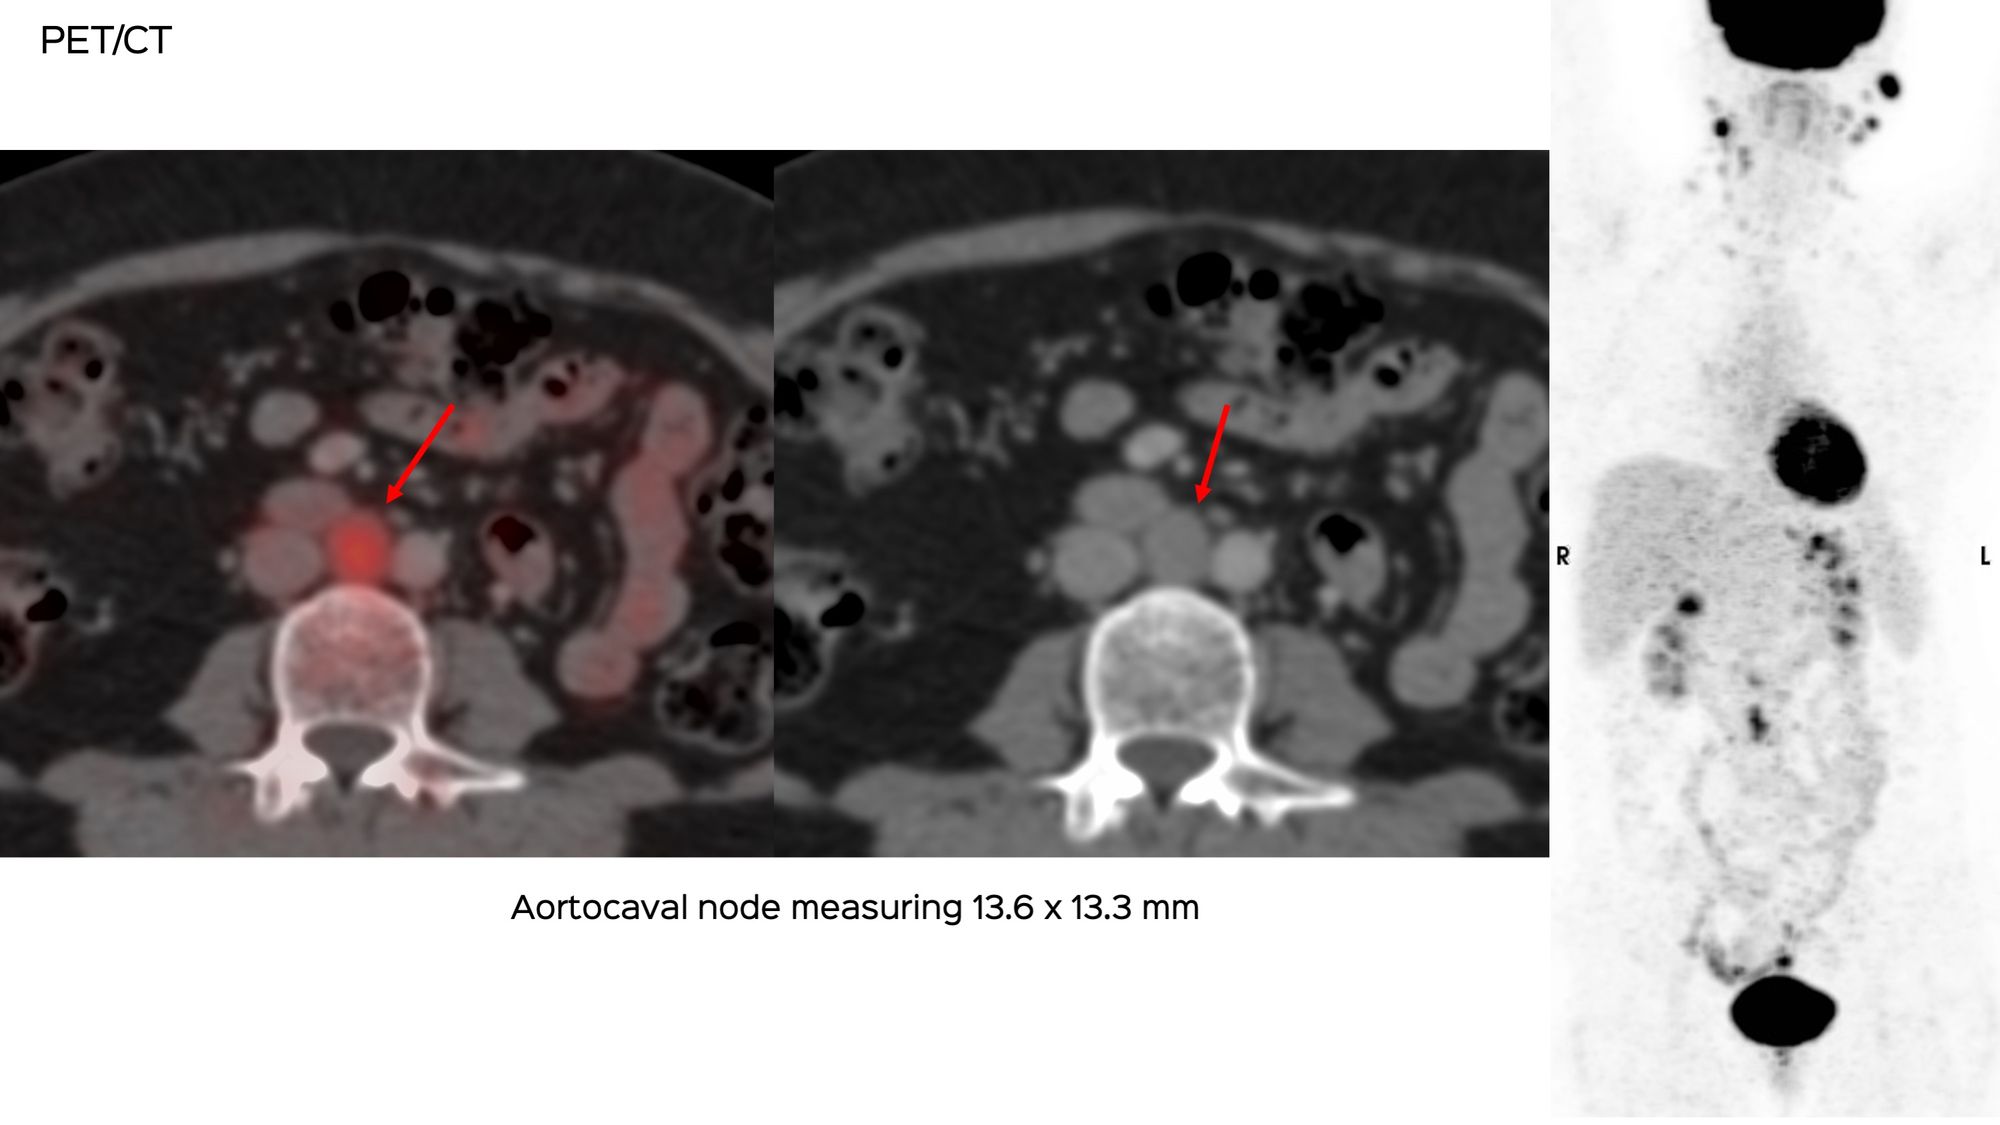

A 45-years old presented with new retroperitoneal nodes. The largest and most active was the aortocaval node.

The medical oncologist asked for a CT guided biopsy.

What route will you take?